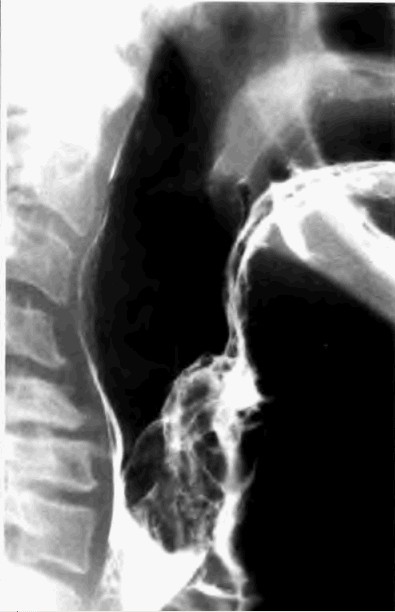

标题: X0954:[贴图]上消造影(有结果)请详细描述

请大家详细描述,本人有些疑惑

片子不错,应该是会厌癌,有条件的话做个ct

会厌癌,点片子的时机抓得很好;正位加粘膜像就更好了。